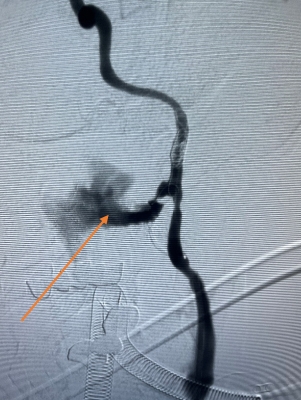

箭头所指为假性动脉瘤

箭头所指为出血点

由于内镜下止血困难,考虑鼻咽癌治疗后并发颈内动脉爆裂综合征大出血,治疗团队立即将患者转入复合手术室。此时,神经外科脑血管病团队早已枕戈待旦,无缝衔接开始手术。面对患者大出血的危急情况,神经外科昝春树主治医师来不及穿戴铅衣,一头扎进抢救工作。股动脉穿刺,微导管、超滑导丝导引导管迅速超选至左侧颈内动脉等系列操作一气呵成。术中造影证实了左侧颈内动脉假性动脉瘤破裂出血,像一股洪流一样持续向外喷出。

“患者左侧颈内动脉后交通动脉粗大,假性动脉近远端已经发生夹层改变。”手术团队凭借丰富的经验,果断决策闭塞左侧颈内动脉,选择大而长的弹簧圈在假性动脉瘤近远端闭塞颈内动脉,成功止住出血。取出咽喉部压迫棉片及棉条均无活动性出血,继续输血、输血浆,予以抗休克治疗。全脑血管造影显示,后交通动脉代偿良好,左侧大脑中动脉血流速度正常,眼动脉显影良好,患者的生命体征逐步恢复正常。见患者情况逐渐平稳,所有人都松了一口气。